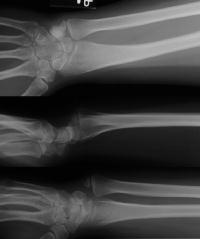

Case 1. Typical Xray findings of congenital Madelungs.

Case 2. Minimal Madelungs picture following pediatric distal radius fracture.